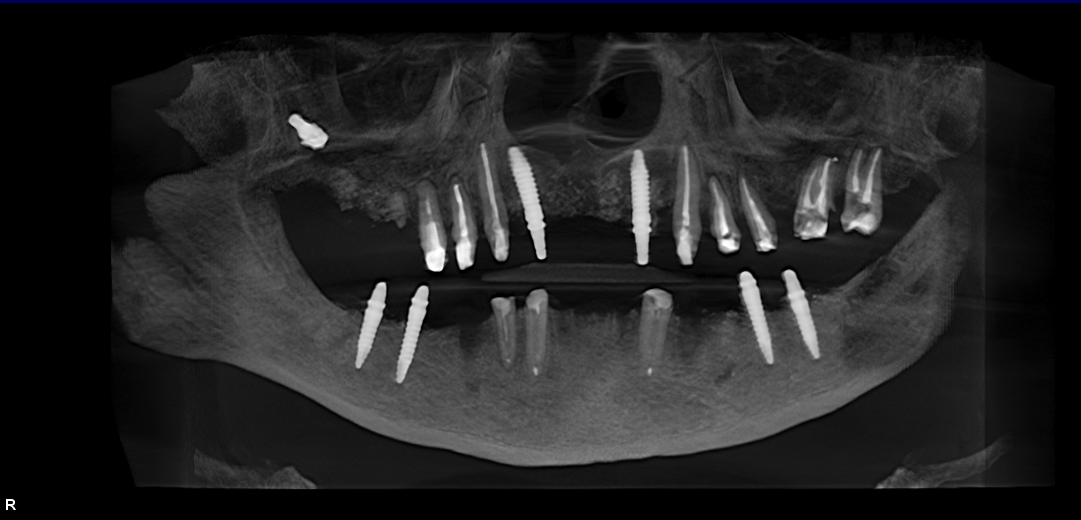

Full-mouth dental implants and prosthetics with sinus lift (upper jaw)

58 y.o, Kazakhstan

Operating dentist: Roh Hyun Ki